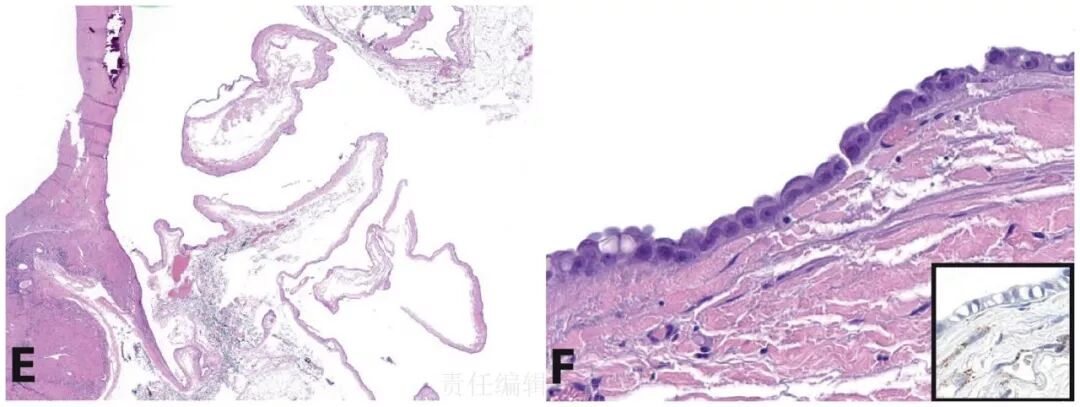

1. HLRCC综合征患者的皮肤平滑肌瘤病,形态特征上并无特殊,但免疫组化FH表达缺失,表皮及皮肤附属器可作为内对照。

子宫平滑肌瘤病一般人群也相对常见,但HLRCC综合征患者相对而言因出现相关症状而切除子宫者年龄要轻10岁左右(一般为30岁左右)。这类平滑肌瘤病细胞学上与HLRCC相关肾细胞癌类似,如细胞密度增加、细胞核出现多形性、胞质内存在嗜酸性颗粒状包涵体。也有HLRCC综合征患者年龄较低即发生子宫平滑肌肉瘤的报道。

2. HLRCC综合征患者的子宫平滑肌瘤病,细胞形态可出现非典型,且常见与HLRCC综合征相关肾细胞癌近似的细胞核特征。免疫组化瘤细胞不表达FH